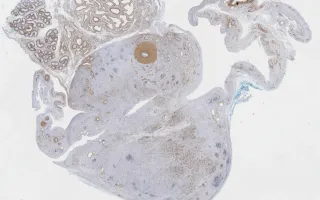

Soft tissue, embryonal rhabdomyosarcoma, SMA stain

By immunohistochemistry the tumor cells are positive for SMA, desmin, and myogenin (MYF4), confirming skeletal muscle differentiation. Molecular testing failed to detect the two most common translocations associated with alveolar rhabdomyosarcoma (PAX3-FOXO1; PAX7-FOXO1), essentially excluding this subtype from the differential diagnosis.

This slide shows SMA stain. See Related Content for H&E, desmin, and myogenin stains.